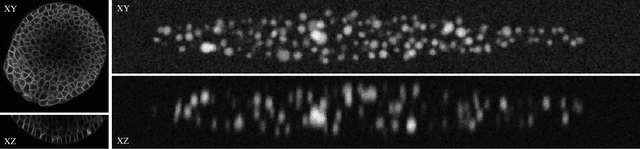

Abstract:Automated image processing approaches are indispensable for many biomedical experiments and help to cope with the increasing amount of microscopy image data in a fast and reproducible way. Especially state-of-the-art deep learning-based approaches most often require large amounts of annotated training data to produce accurate and generalist outputs, but they are often compromised by the general lack of those annotated data sets. In this work, we propose how conditional generative adversarial networks can be utilized to generate realistic image data for 3D fluorescence microscopy from annotation masks of 3D cellular structures. In combination with mask simulation approaches, we demonstrate the generation of fully-annotated 3D microscopy data sets that we make publicly available for training or benchmarking. An additional positional conditioning of the cellular structures enables the reconstruction of position-dependent intensity characteristics and allows to generate image data of different quality levels. A patch-wise working principle and a subsequent full-size reassemble strategy is used to generate image data of arbitrary size and different organisms. We present this as a proof-of-concept for the automated generation of fully-annotated training data sets requiring only a minimum of manual interaction to alleviate the need of manual annotations.